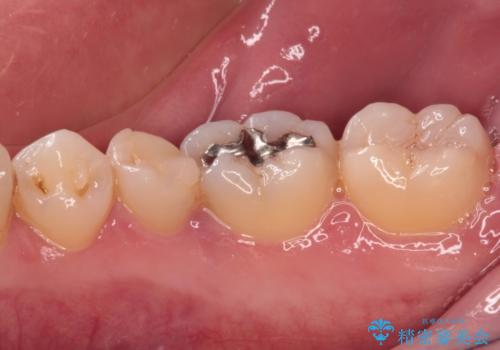

治療について

根管治療後9ヶ月で撮影したレントゲン写真より、歯根周辺の透過像が十分に消失している様子が認められました。